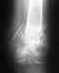

Здравствуйте, 3 месяца назад ,не сильно упал вроде бы,но спустя месяц начали тревожить немного боли, обходил кучу травматологов у себя в городе, поехал в областную больницу. В итоге: хирург-проктолог сказал ,что копчик в ходячем состоянии, как после перелома ( но при переломе я бы вряд-ли смог ходить и сидеть, а такого не было), травматологи говорят разное : подвывих поставили диагноз, кто-то говорит загиб с рождения быть может и ничего точного никто не говорит, диагноз " травматическая кокцигодиния". Прикреплю снимки КТ и рентгена. Скажите есть ли что-то на снимках? Думаю пойти на отчаянный шаг, пойти к мануальному доктору, но смущает ,что вправляет без предв.снимка и анестезии. Боюсь сделать хуже